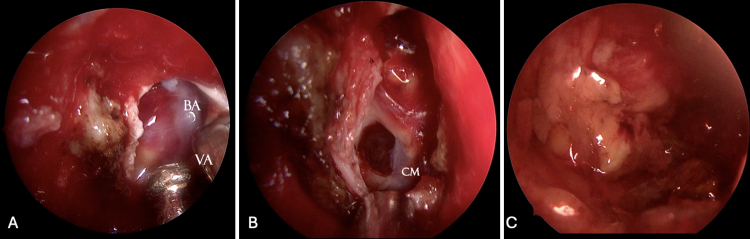

Observations: The authors report the case of a 54-year-old woman with a ventral pontine cavernous malformation (CM) presenting with recurrent hemorrhagic episodes, all resolving without neurological sequelae. Based on the anterior midline location of the lesion within the pons and the posterolateral displacement of the corticospinal tracts (CSTs) on preoperative tractography, an EETA was deemed the most suitable approach. Gross-total removal was achieved without neurological worsening or postoperative CSF leakage.

Lessons: This case supports the use of EETA as a safe and effective surgical route for ventral pontine CMs with anterior surface presentation. Accurate preoperative planning, including assessment of CST displacement via diffusion tensor imaging, and direct intraoperative cortical stimualtion are essential for identifying a safe entry point. Although technically demanding and not universally applicable, EETA offers a direct surgical corridor that minimizes neurovascular manipulation and facilitates favorable outcomes in selected cases. https://thejns.org/doi/10.3171/CASE25356.